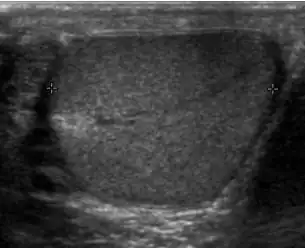

Primary leukemia of the testis is rare. However, due to the presence of blood-testis barrier, chemotherapeutic agents are unable to reach the testis, hence in boys with acute lymphoblastic leukemia, testicular involvement is reported in 5% to 10% of patients, with the majority found during clinical remission. The sonographic appearance of leukemia of the testis can be quite varied, as the tumors may be unilateral or bilateral, diffuse or focal, hypoechoic or hyperechoic. These findings are usually indistinguishable from that of the lymphoma [Fig. 9].

Fig. 9. Leukemia. Diffuse hypoechoic infiltrative lesions are seen involving the whole testis, indistinguishable from that of the lymphoma.